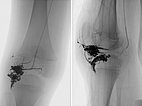

Nach erfolgreicher Embolisation der beiden AVM-Nidusanteile zeigt sich in den Röntgenübersichtsbildern (links a.-p., rechts seitliche Projektion) ein vollständiger Ausguss der beiden Anteile durch das Embolisat, der sogenannte Cast. Dieser besteht aus Ethylen-Vinyl-Alkohol-Kopolymer.

Abschluss-DSA-Bild (links a.-p., rechts seitliche Projektion) nach Beendigung der erneuten Embolisation zeigt wiederum angiographisch einen vollständigen Verschluss der beiden Anteile der AVM.